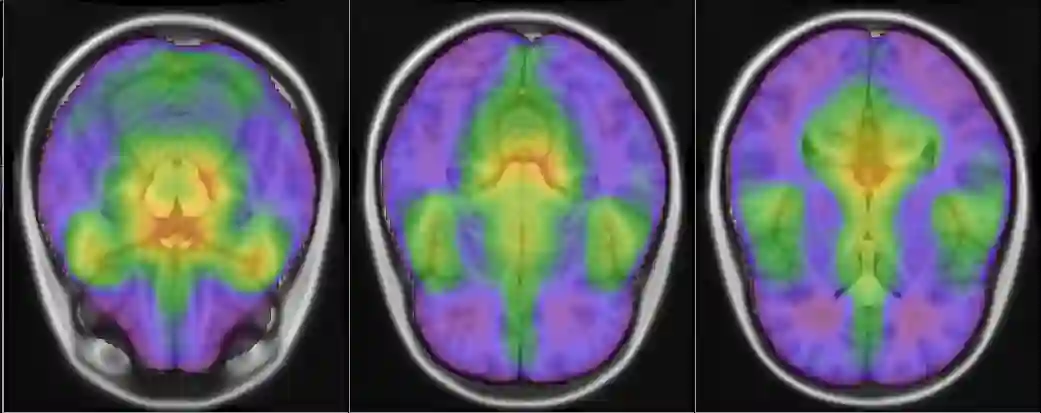

Representational similarity analysis (RSA) is a multivariate technique to investigate cortical representations of objects or constructs. While avoiding ill-posed matrix inversions that plague multivariate approaches in the presence of many outcome variables, it suffers from the confound arising from the non-orthogonality of the design matrix. Here, a partial correlation approach will be explored to adjust for this source of bias by partialling out this confound. A formal analysis will show the dependence of this confound on the temporal correlation model of the sequential observations, motivating a data-driven approach that avoids the problem of misspecification of this model. However, where the autocorrelation locally diverges from the volume average, bias may be difficult to control for exactly (local bias), given the difficulties of estimating the precise form of the confound at each voxel. Application to real data shows the effectiveness of the partial correlation approach, suggesting the impact of local bias to be minor. However, where the control for bias locally fails, possible spurious associations with the similarity matrix of the stimuli may emerge. This limitation may be intrinsic to RSA applied to non-orthogonal designs.